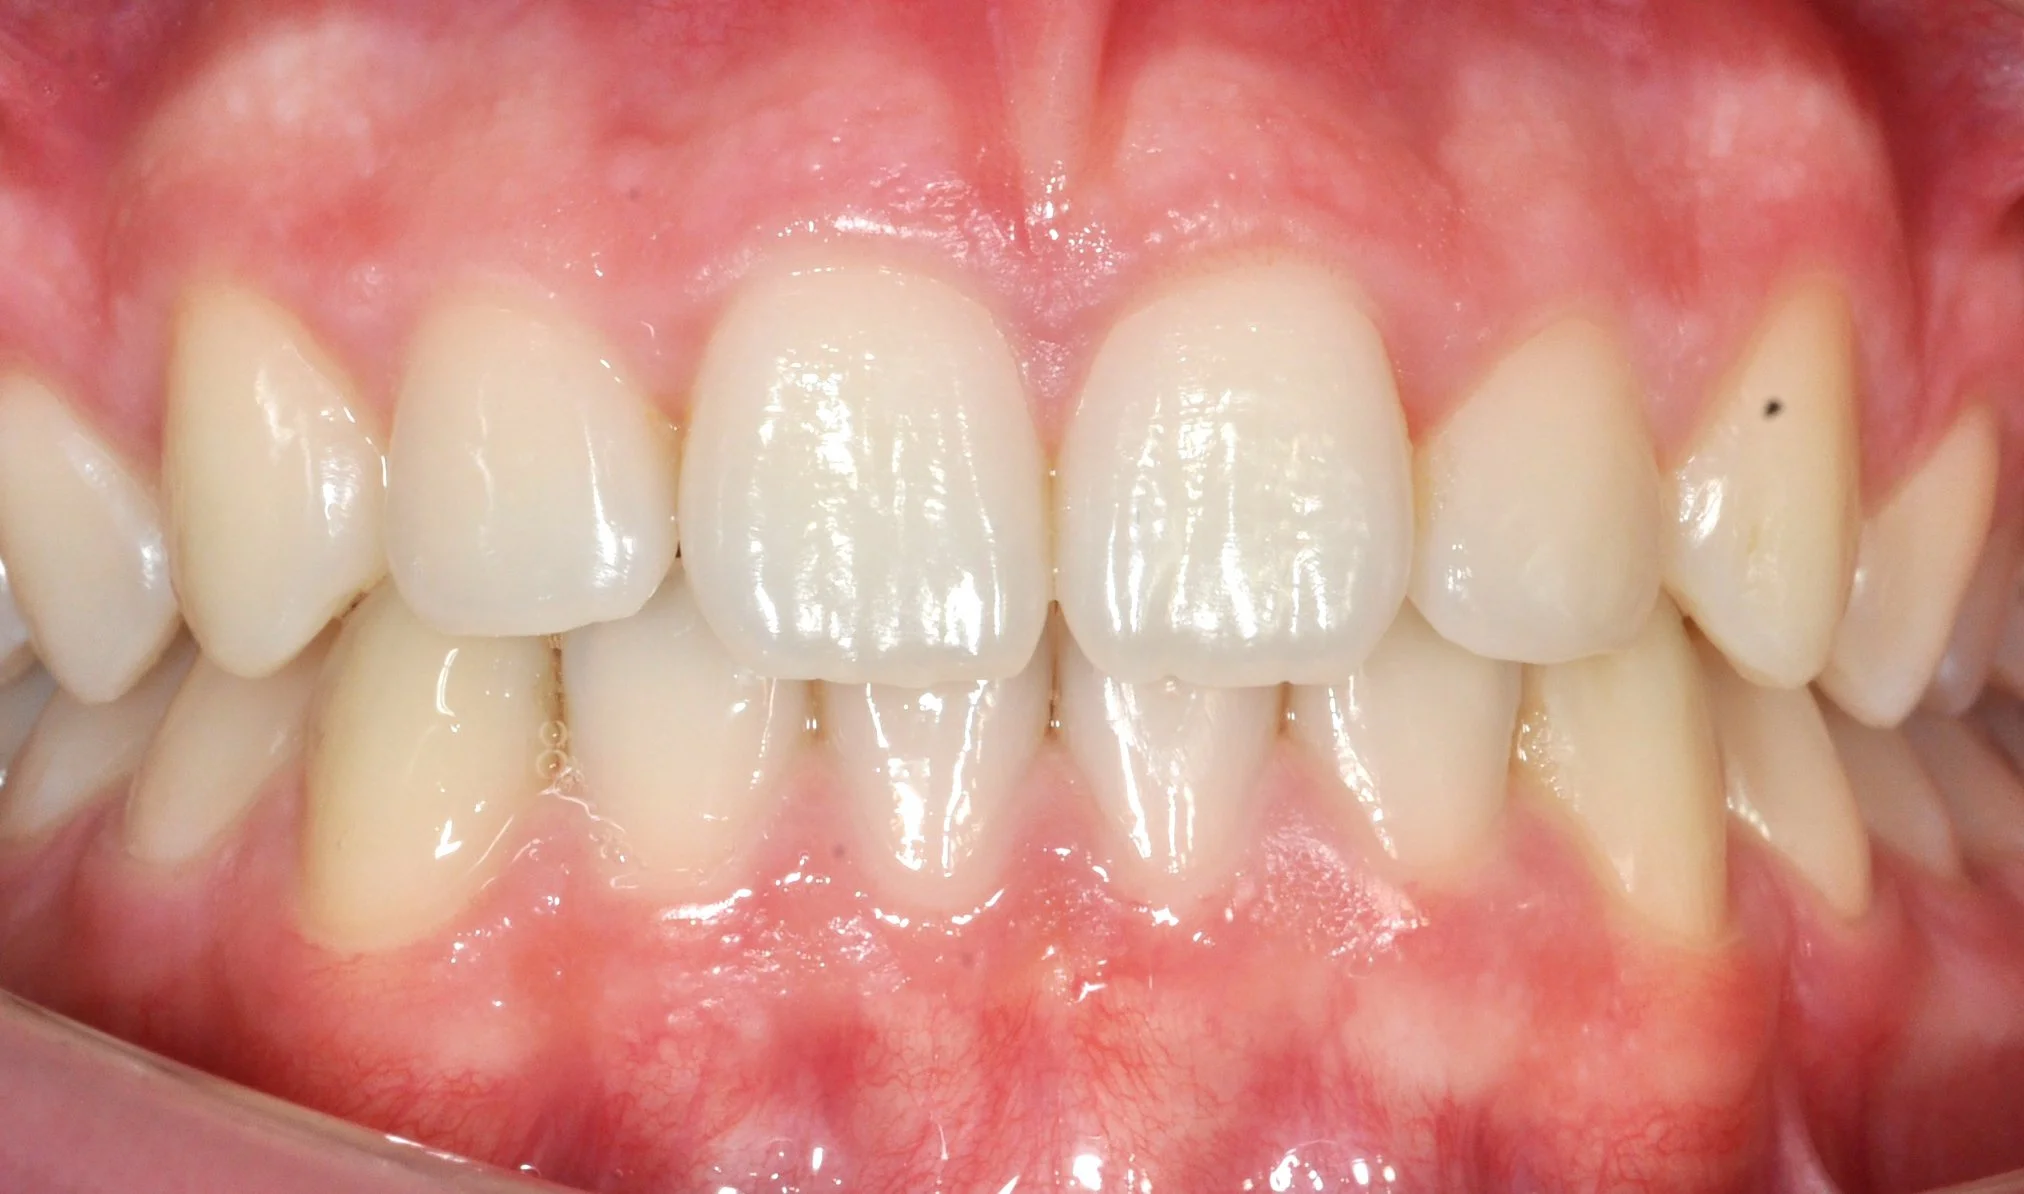

PRIMA

DOPO